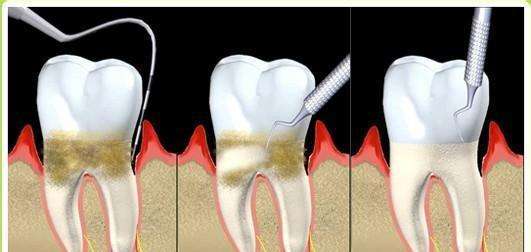

洗牙之后牙縫會變大嗎?實際上這個是犯了邏輯錯誤問題。不是洗牙導致牙縫變大的,而是洗牙時把牙縫中的牙結石去掉了,因此你感覺牙縫中變空變大了,這是因為牙縫本來就被牙結石占據導致變大的。

本來我們的牙齒牙縫是很小的,牙齒都緊挨著,但是慢慢地,因為有時一些食物殘渣殘藏在牙縫中,刷牙也難以全方位、無縫隙的清除到位,久而久之形成了牙結石,而當我們把這些牙結石去掉之后,原本牙結石的位置空了,就會顯得牙縫特別大。

這個感覺其實是跟有牙結石的時候對比的感受,但你想過嗎?有的牙結石是很大的一片,去掉后肯定十分明顯是會感覺到空的,但大概兩周左右就不會再有那種“牙縫特別大”的感覺了,大概是習慣了吧。

其實,洗牙的好處就是把你牙縫中的牙結石清除干凈,預防口腔疾病,而牙結石,通常是很硬的,一旦形成,即使你刷牙也刷不掉。